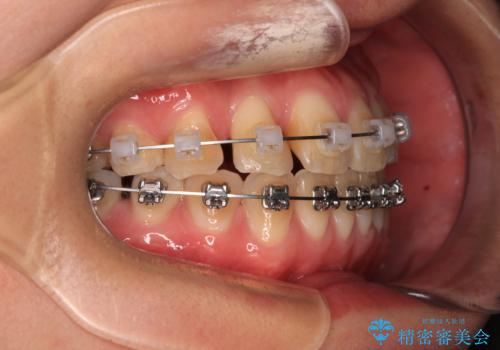

- 矯正装置

- メタルブラケット

舌の突出癖により、治療過程でスペースが多くできましたが、舌のトレーニングを頑張っていただき、1年強で終えることができました。